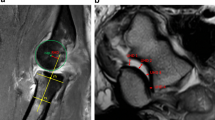

There has been lively debate regarding the injury mechanism and treatment rationale of terrible triad injuries for more than a century. Hotchkiss et al. [1] first defined an injury pattern involving the radial head and coronoid process in the setting of an elbow dislocation; they coined it “the terrible triad injury” (TTi) because of the poor treatment outcomes, including recurrent instability, stiffness, post-traumatic arthrosis, and chronic pain (Fig. 1).

Terrible triad injury of the elbow. In 1996, Hotchkiss et al. [1] defined an injury pattern involving fracture of radial head and coronoid process, in the setting of an elbow dislocation (black circles). The authors termed this injury “the terrible triad of the elbow.” Further study has led to the discovery that the lateral ulnar collateral ligament (LUCL), anterior band of the medial collateral ligament (aMCL), and/or the common flexor-pronator and extensor tendons (grey circles) are also frequently injured in TTs of the elbow. Furthermore, these latter injuries allow us to determine overall injury severity and can also help guide treatment

Based on their clinical experience, in 1996, Hotchkiss et al. [1] described an injury pattern involving the radial head and the coronoid process in the setting of a dislocated elbow and called it the terrible triad injury because of the poor reported outcomes, including recurrent instability, stiffness, post-traumatic arthrosis, and chronic pain (Fig. 1).